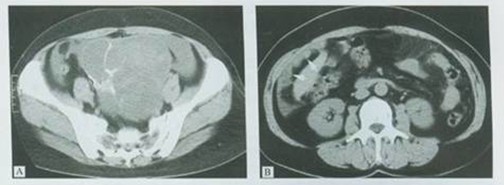

【检查】住院后行全腹CT检查,结果:双侧附件区占位符合囊腺瘤CT表现。较大者10.9*9.5cm,囊壁厚薄不均,内见多发分隔,病变填充盆腔,子宫及膀胱受压。肝脏多发压迹,腹膜广泛增厚并大网膜增厚,提示腹膜及大网膜转移瘤。盆腹腔大量积液。脐疝。 双肺下叶多发局灶性纤维化,右肺门及纵隔淋巴结钙化。

CT检查病变占位符合囊腺瘤表现

【诊断】考虑卵巢癌并腹膜广泛转移累及脐部,腹水。

【复查】患者治疗2个疗程后,CT检查腹水症状大幅减少,但并未消失。

【回访】两月后再次检查,肿瘤标志物明显缩小,瘤体缩小变为8.7*6.9cm,腹水症状基本消失。陈女士表示目前精神状况良好,食欲有所增加,体重略有上升,疼痛症状缓解。陈女士感谢WB-1无创全身热疗系统提高了她的生活质量,延长了生存期。